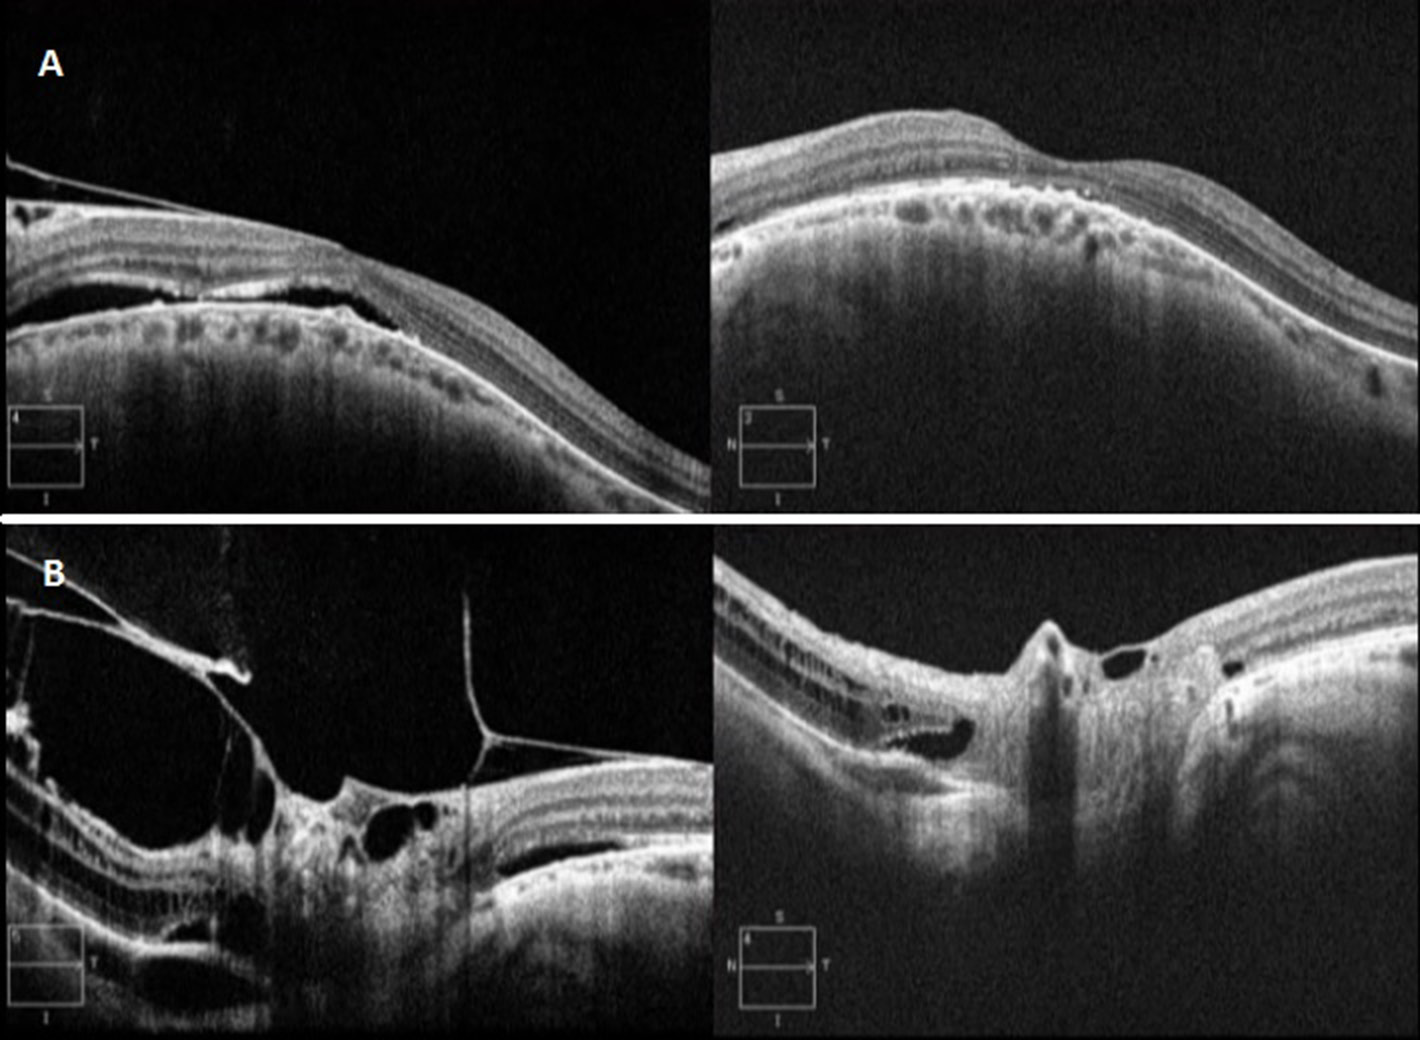

All patients showed postoperative improvement in visual acuity (Table 2). No decrease in IOP below 10 mm Hg was documented on postoperative day 1. Furthermore, no postoperative complications were recorded during the six-month follow-up, and evident improvement of the anatomical status was confirmed using OCT in all cases (Figure 1).